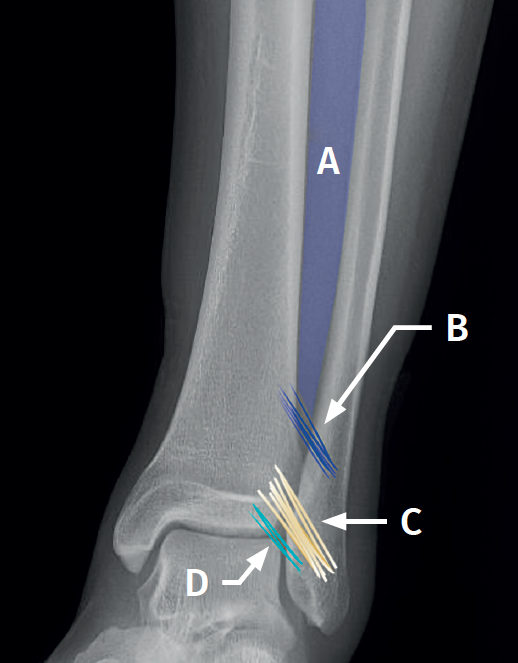

Surgical technique: arthroscopic treatment of acute syndesmosis injuries

The technique should be performed using the conventional anteromedial and anterolateral portals. The anteromedial portal is used for visualization, while the anterolateral portal serves as the working portal. Once the tibiofibular space is visualized, the inflamed synovial component is resected with an arthroscopic shaver to facilitate reduction (Figure 7A). Then, under direct vision, we restore the tibiofibular space, carefully taking into account possible malrotation of the fibula, especially in Maisonneuve type fractures. For fibular reduction we use a Verbrugge clamp, which allows us to correct the rotation. In our experience, once the space has been cleaned and if the position is correct, it is infrequent to have to use a compression clamp between the tibia and fibula.

Once the desired reduction has been achieved, we visually check the position and temporarily fix it using a Kirschner pin.

For definitive fixation, the surgical options range between rigid fixation with screws and dynamic fixation. Screws have been the standard procedure for decades, but involve complications, such as loosening or rupture. Furthermore, some surgeons advocate their removal, with the inherent risk of recurrence of instability(27). Dynamic fixation was designed to overcome some of these problems by allowing a degree of physiological movement of the syndesmosis, facilitating early weight bearing, reducing the risk of rupture, and eliminating the need to remove the implant (Figure 7B).

Grassi et al., in a meta-analysis involving over 300 patients, demonstrated an overall decrease in the relative risk of complications (RR = 0.55, p = 0.003) with dynamic systems(28). Raeder et al., in a randomized trial of 97 patients contrasting screw fixation versus a dynamic system, reported a lower incidence of osteoarthritis with suture buttons of 65% versus 35% (p = 0.009) at 5 years(29). Suture button constructions afford a degree of micro-mobility, mimicking physiological mobility, which can promote ligament healing. Likewise, flexible implants are better able to tolerate an imperfect reduction, as a possible complication, even if arthroscopic control of the joint is performed.